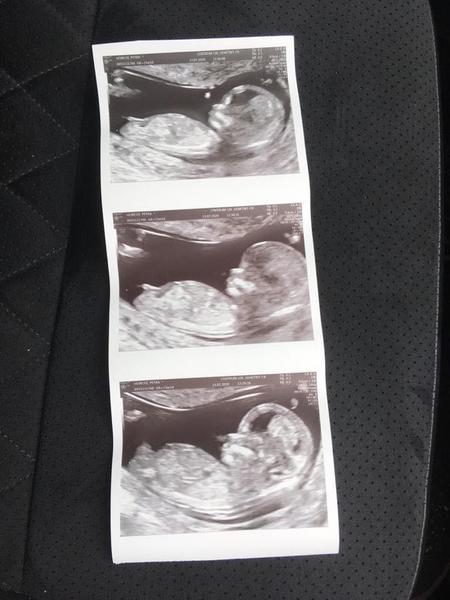

Foto z ultrazvuku. Holčička nebo klučík?

Hezký večer, dnes jsme byli na screeningu v prvním trimestru, paní doktorka nám řekla pohlaví s jistotou 90%, nicméně prý už se takhle jednou sekla, tak by mě, čistě ze zvědavosti, zajímalo, co myslíte vy? Mě to podle toho co jsem na internetu vyčetla sedí s paní doktorkou, ale víte jak, sem baba zvědavá 🙂

Z fotky z profilu se to nedá poznat. Nemáš přímo ultrazvuk dolních partií? 🙂 Nám doktor vyfotil přímo genitálie.

takhle to poznala i doktorka, pak mrkla zespodu mezi nožky a ještě si to jakoby potvrdila, ale v 1.trimestru se to poznává právě podle fotky z profilu 🙂

tak paní doktorka říkala, že to bude na těch 90% holčička